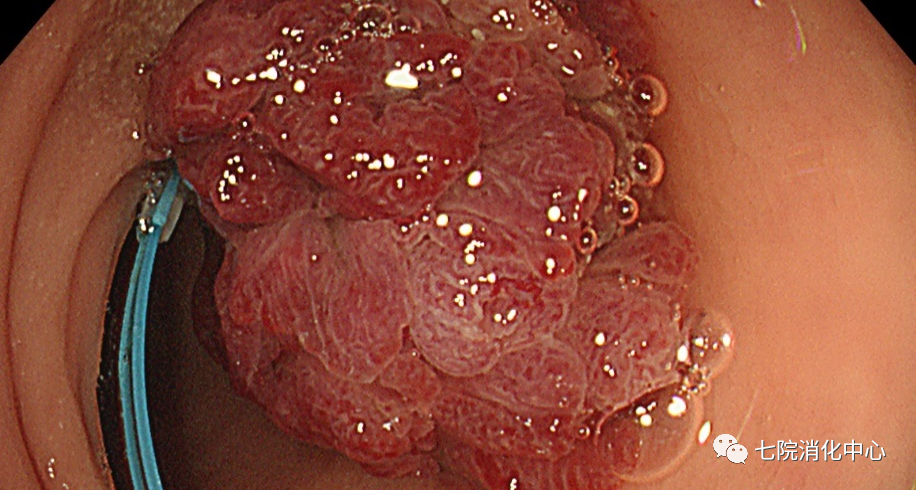

王阿姨今年65岁,前段时间总感觉肚子不舒服,大便带血,每天的排便习惯也有改变,于是来到交大附属胸科医院消化中心就诊,接诊的消化科副主任张蓉在了解其病情后,将其收治入院。入院后肠镜检查发现,其肠道内多发大小不等息肉,最大直径1.8cm.医生当即对息肉进行了切除处理,病理提示管状绒毛状腺瘤伴低级别上皮内瘤变,但庆幸的是发现较早,目前王阿姨已经康复出院,之后只需要每半年复查一次肠镜。

EMR:

常用于切除无蒂息肉,通过注射缓冲液到黏膜下层的空间,使上皮与底层组织分开,使病变分离。包括整块切除和分次切除,目前黏膜下注射切除法是最常用的一种EMR切除法,其他EMR切除方法还有透明帽辅助EMR、注水法/水下法EMR等,EMR在实现大肠息肉的完整内窥镜切除术方面明显优于冷圈套器,但它需要黏膜下注射和电灼,因此不可避免出现延迟出血、息肉切除术后综合征和穿孔等并发症。